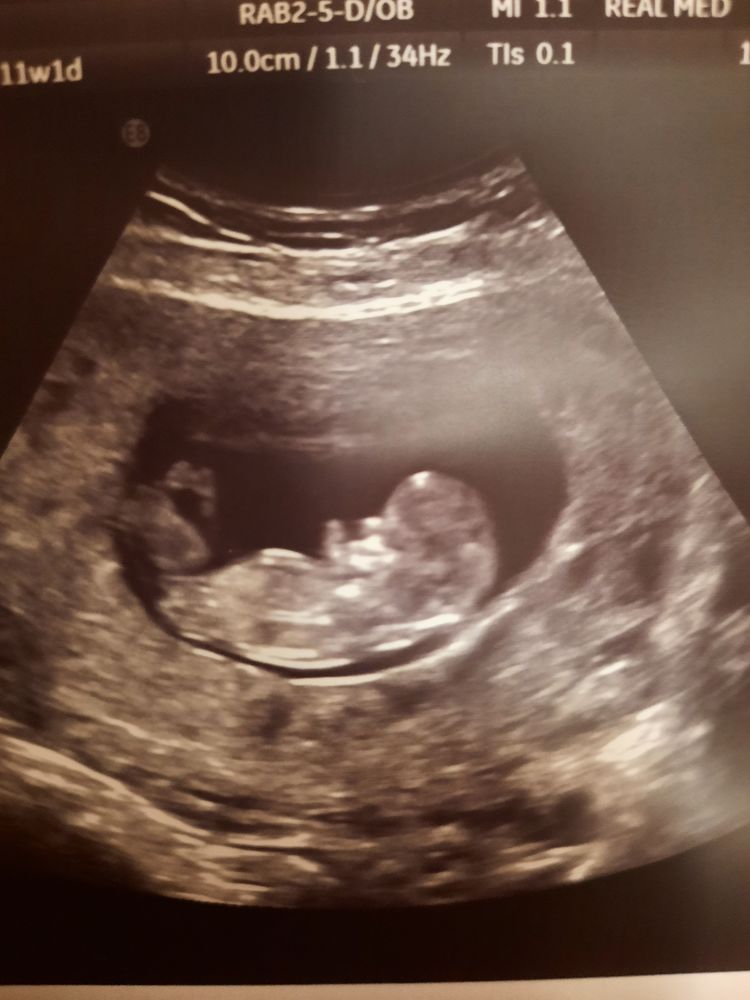

Здравствуйте! Девочки! Кого вы видите? 2й скрининг через дней 10. Качество фото конечно желает лучшего.

По бугорку девочка, но всё-таки я бы не делала поспешных выводов. У меня в 11,1 у малыша был такой же бугорок, а ровно через неделю в 12,1 на скрининговом узи уже был задран вверх, как у мальчика. Но я перед этим кровь сдавала, поэтому рано узнала, что у меня мальчик)

Мечтаю о дочке, ну у девочек бугорок параллельно спинке, у мальчишек больше задран вверх. Но опять же это с определённого срока. Вот мое узи 11 н 1 д .

Через неделю пришла в 12 и 1, уже наверх торчал, фотки нет, к сожалению, но прям видно было. Сейчас уже проще кровь сдать (с 10 недель можно) , чем угадывать по узи.